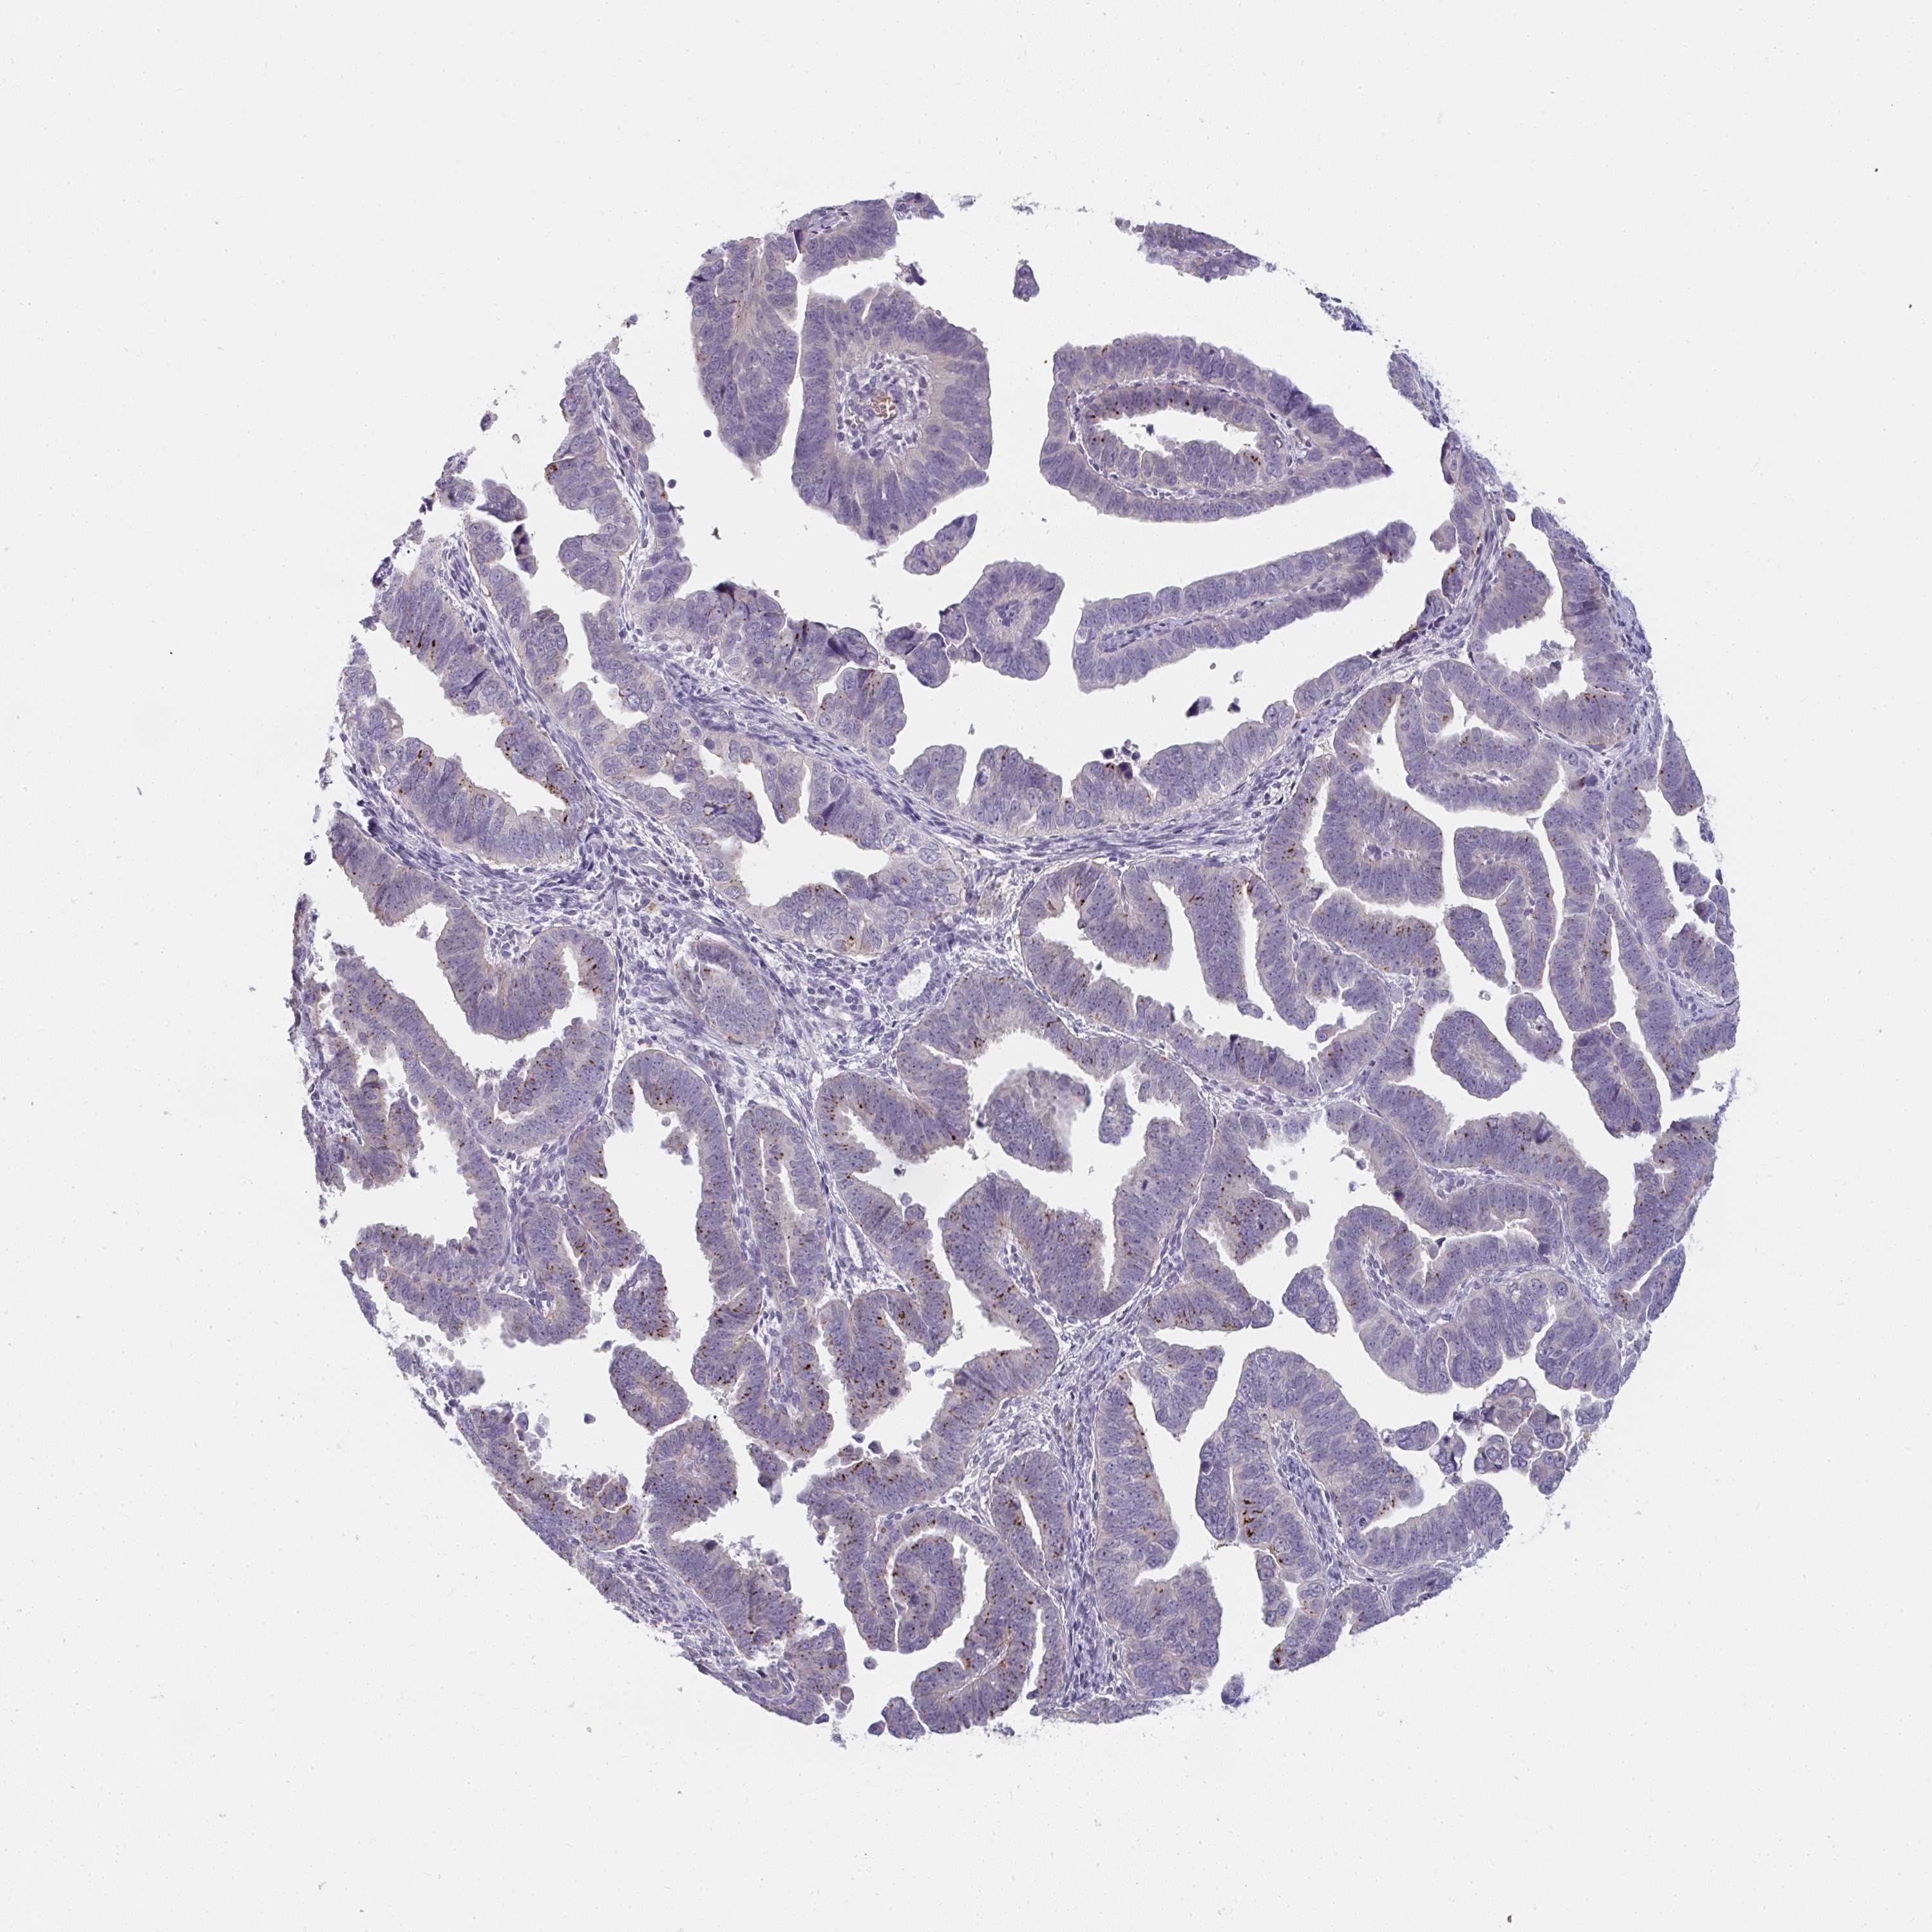

ENDOMETRIAL CANCER - Protein expressioni

A mouse-over function shows sample information and annotation data. Click on an image to view it in a full screen mode. Samples can be filtered based on level of antibody staining by selecting one or several of the following categories: high, medium, low and not detected. The assay and annotation is described here.

Note that samples used for immunohistochemistry by the Human Protein Atlas do not correspond to samples in the TCGA dataset.

Antibody stainingi

Antibody staining in the annotated cell types in the current human tissue is reported as not detected, low, medium, or high, based on conventional immunohistochemistry profiling in selected tissues. This score is based on the combination of the staining intensity and fraction of stained cells.

Each image is clickable and will lead to virtual microscopy that enables deeper exploration of all samples and also displays staining intensity scores, fraction scores and subcellular localization as well as patient and tissue information for each sample.

Antibody HPA049911

Antibody CAB010161